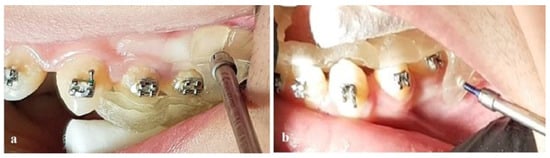

2. Materials and Methods